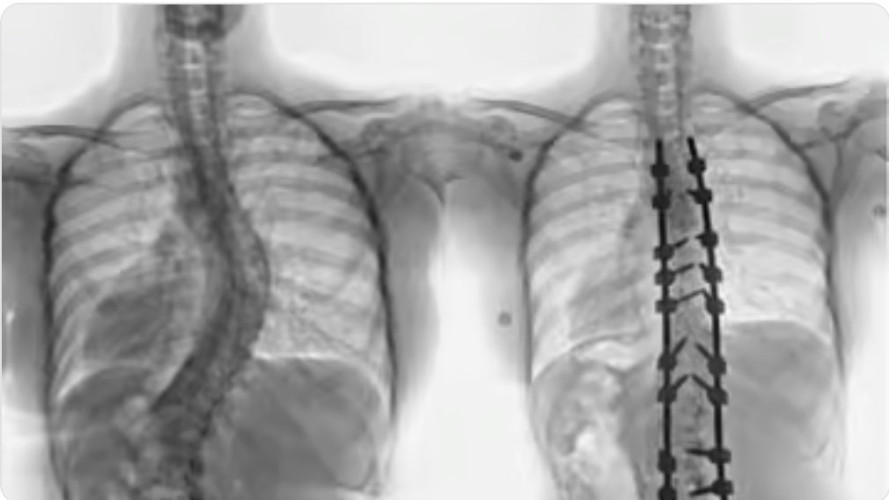

وقال د. خليفة أن المريضة راجعت المستشفى وهي تشتكي من انحناء جانبي للعمود الفقري منذ صغرها، بدأت مؤخراً تعاني من آلام بالظهر، إضافة إلى صعوبة في ممارسة الحياة الطبيعة، أدت هذه الأعراض إلى تغيير نمط حياتها والحد من حركتها، وفور وصولها إلى المستشفى أجريت لها التحاليل والفحوصات الطبية الدقيقة، التي بينت إصابتها بحالة انحراف “جنف” مضاعف بدرجة الـ”60″ للفقرات الصدرية، ودرجة 50 للفقرات القطنية ودرس الفريق الطبي الحالة على ضوء نتائج الفحوصات والتحاليل، وخلص إلى ضرورة التدخل الجراحي لعلاج العيوب، والحد من المضاعفات، وبعد اتخاذ كافة التدابير الطبية اللازمة لمثل هذه الحالات المعقدة، أخضعت الشابة لعملية جراحية، تم فيها تقويم العمود الفقري بعدد “20” من البراغي والقضبان المعدنية والطعوم العظمية الصناعية وتثبيت ودمج الفقرات، واستخدمت في العملية التي استمرت لـ”4″ ساعات، مع فريق تخدير متمرس ومراقبة أعصاب وفريق تمريض ماهر إضافة الى مجموعة من أحدث الأجهزة الطبية التي ساهمت مع الكوادر الطبية عالية الكفاءة والتأهيل بالمستشفى في إنجاحها.

ونقلت المريضة الى جناح التنويم بعد العملية، وبدأت حالتها في التحسن باضطراد بعد خروجها من غرفة العمليات، إذ استطاعت المشي بتوازن بعد أقل من “24” ساعة من العملية مع فريق العلاج الطبيعي المتمرس، واستعادت قدرتها على الاستلقاء والنوم على ظهرها، فضلاً عن القوام والمظهر الطبيعي، بعد تعديل وضعية الحوض والكتف، كما أن طولها مع النجاح الكبير للتعديل زاد بحدود “3” سم، وخرجت من المستشفى وهي بصحة جيدة، وتوقع أن تستعيد كامل عافيتها سريعاً مع الإنتهاء من برنامج العلاج الطبيعي.